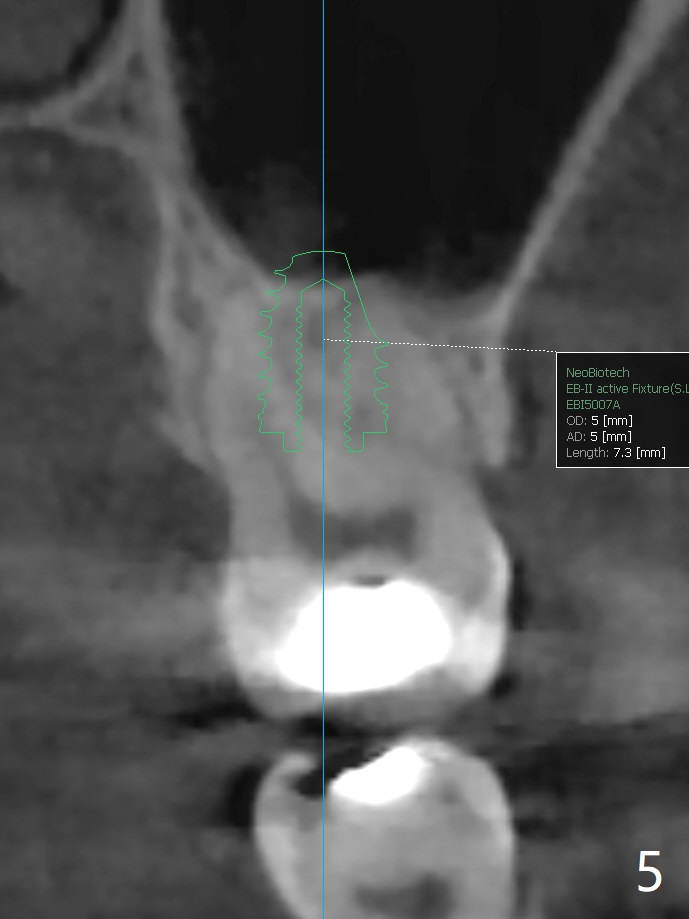

57岁女缺失2号牙多年,八年前14号牙折裂,根管治疗失败,改为即种(徒手),上颌骨骨质高度不足(图一),植体就一定植入上颌窦?近来15号牙又怀疑折裂,不愿接受根管治疗,要求种植。其实14号牙植体植入腭侧牙槽窝,顶端还有骨质,根尖颊侧多个螺纹似乎没有骨质覆盖,但是没有症状。15号牙上端上颌窦膜薄(图三),如果提升时窦膜完整,植入5x8.5毫米植体(图四),否则放置PRF,胶原塞,可以不植骨,植入5x7.3毫米植体(图五)。